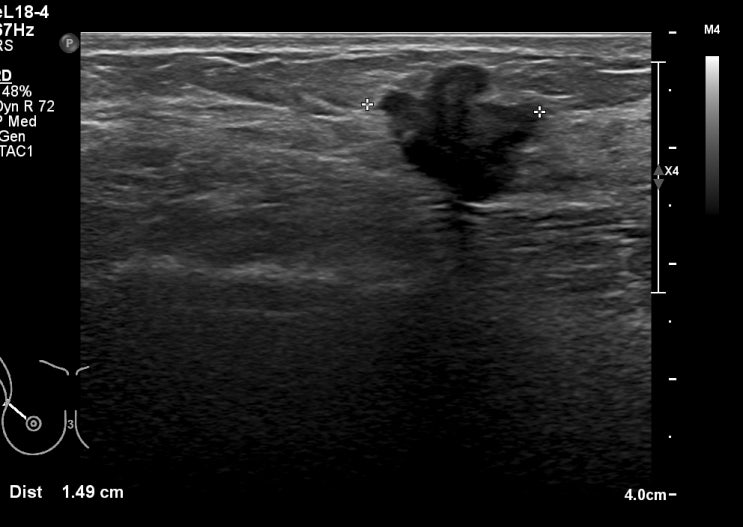

유방 미세석회화의 중요성 / 23년 가장 뿌듯한 케이스

저는 유방촬영술을 아주아주 중요하게 생각하는 영상의학과의사입니다. 제 블로그 유방관련글을 관심있게 ...

유방암 검진 2023년 가장 기억에 남는 케이스

새로운 병원에서 1년을 보냈습니다. 맛있는 밥과 좋은 직장동료들 덕에 올한해 너무너무 행복하게 보냈는데...